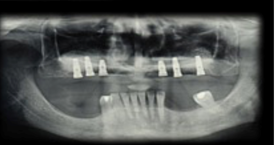

Workshop 3 - Short implants or sinus floor elevation

The use of dental implants to replace missing teeth is a safe and effective long-term treatment, given the high predictability of osseointegration. Nowadays, implants are placed where the rehabilitation is required. In all cases, bone availability is one of the reasons for concern for clinicians at the time of implant placement. The different areas in both jaws present their own challenges regarding the ideal location to place the implant. Bone with sufficient height and width, and of good quality, is essential for the correct placement of implants, so they can support a dental prosthesis.

The aim of this workshop was to assess the posterior maxillary area. The posterior maxilla naturally presents low-height alveolar process, which is anatomically limited by the maxillary sinus. The roots of the molars are closely related to the floor of the maxillary sinus. In the center of the alveolar crest we find the root trifurcation area, which is the ideal site for implant placement from a prosthetic perspective, and where there is the lowest bone height in the sinus floor. This means that placing implants of standard dimensions after tooth loss

The resorption processes resulting from such loss, common to all regions of the alveolar process, may aggravate this situation. Maxillary sinus pneumatization, on account of increased osteoclastic activity along the sinus membrane and the absence of a dental “barrier” facing changes in sinus air pressure, may affect the morphology of the site. These conditions pose an anatomical challenge to the treatment of the edentulous posterior maxilla using dental implants. The techniques to repair defects in the residual alveolar ridge with autologous bone graft procedures have predictable results, which are described in the literature. A factor that explains their good results is that there are no immune reactions that may interfere with the process of tissue remodeling and development. They intrinsically have osteoblasts and growth factors responsible for the cellular changes that occur after implantation, and that end with remodeling and bone formation at the site1. Its disadvantage is the need for an additional donor surgical area which can be intraoral, in cases in which the need for reconstruction is small, or extraoral in cases of medium-sized or large reconstructions. In the 1980s, bone grafting techniques in the maxillary sinus were used to solve the problem of lack of bone, and to allow for implant placement. One of the techniques described is surgery to lift the floor of the maxillary sinus, known by its name in English: Sinus Lift2,3.

Various alternatives to the technique and different types of grafts and biomaterials of different nature have been proposed as an alternative to autogenous bone to fill the cavity resulting from the elevation of the sinus floor. The application of biomaterials has been encouraged given its ease of use and technique with a very good clinical performance, and the limited supply of autogenous bone in relation to the necessary volume for a sinus lift. Philip Boyne2 (1983) describes the reconstruction of fractures with bovine bone. His studies were part of the development of inorganic bovine bone: material which is very similar to human bone. Studies conducted on animals suggest that deproteinized bovine bone is resorbed and gradually replaced by viable bone tissue. It is a slow process compared with autografts4, which helps preserve the macrostructure rebuilt in the replacement process. Depending on bone availability (height and width) in the posterior maxillary area, the options for placing implants in the right place are: